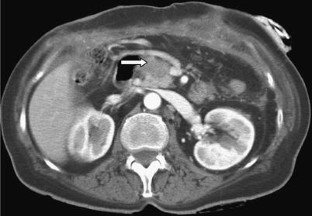

Bei einer 63-jährigen Patientin mit o. g. Risikofaktoren, einem Pancreas divisum und vermeintlichem zystischen Pankreasschwanztumor, der sich als Pseudozyste bei einer Pankreatitis herausstellte, erfolgte eine 2-jährige Behandlung rezidivierender Pankreatitisschübe. Erst bei der Behandlung eines komplizierenden Leberabszesses fiel in einer CT eine malignitätssuspekte, zum Aufstau des Pankreashauptganges führende Pankreaskopfraumforderung auf. Retrospektiv waren Gangveränderungen schon auf Voraufnahmen sichtbar. Die partielle Duodenopankreatektomie bestätigte das Pankreaskopfkarzinom.

A 63-year-old female patient with suspected cystadenocarcinoma of the pancreas tail, which was resolved as a pancreatic pseudocyst, was treated for recurrent pancreatitis for 2 years. A tumor in the pancreas head was only detected on a follow-up CT after resection of a complicating liver abscess. In retrospect, progressive pancreatic duct anomalies were visible on previous scans. Partial duodenopancreatectomy confirmed the presence of a pancreas head carcinoma.